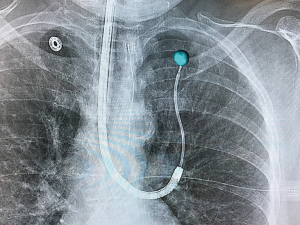

The latter study utilized the Philips Allura Xper FD20 system with the OncoSuite software package. This combination allows for the physician to select the lesion on the initial CBCT scan and it is then projected on standard fluoroscopy throughout the case in what is referred to as augmented fluoroscopy. The projected lesion is accurately projected during any rotation of the c-arm throughout the case. This allows for accurate localization of the lesion as well as real-time confirmation of biopsy tools (Figure 1). Additionally, this allows for non-fluoroscopically visible lesions to now be visible. Most importantly, 3D real-time imaging is able to overcome CT-to-body divergence issues that plague current forms of navigational bronchoscopy. As the field advances toward the possibility of bronchoscopic ablation of peripheral tumors, real-time confirmation of probe positioning will be imperative.